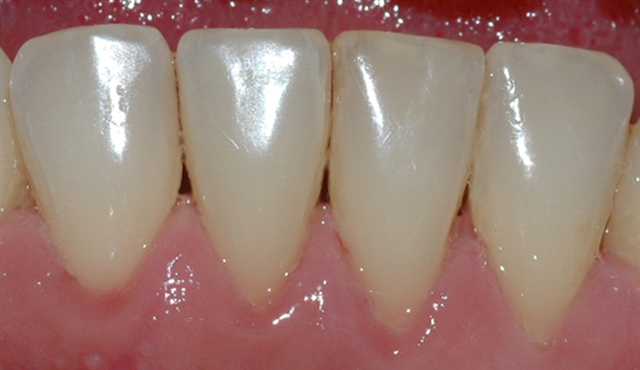

• Biletet viser tilsynelatande normale tannkjøttilhøve ved tenner i underkjeven.